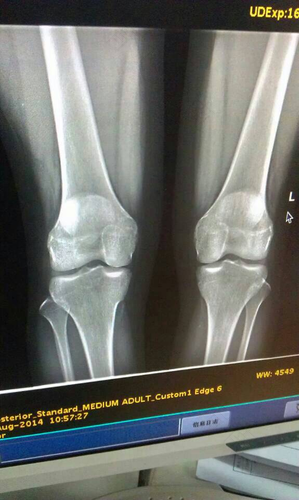

1、临床上一般的情况下,当孩子的年龄已经达到16周岁以后,四肢的骨骼就开始出现闭合的现象,在18岁以后就已经闭合完成,在这之前如果想要判断复合线是否出现了闭合的状况,就可以找专业的医院对腿部的骨骼,拍一个x线片,让专业的医生查看。